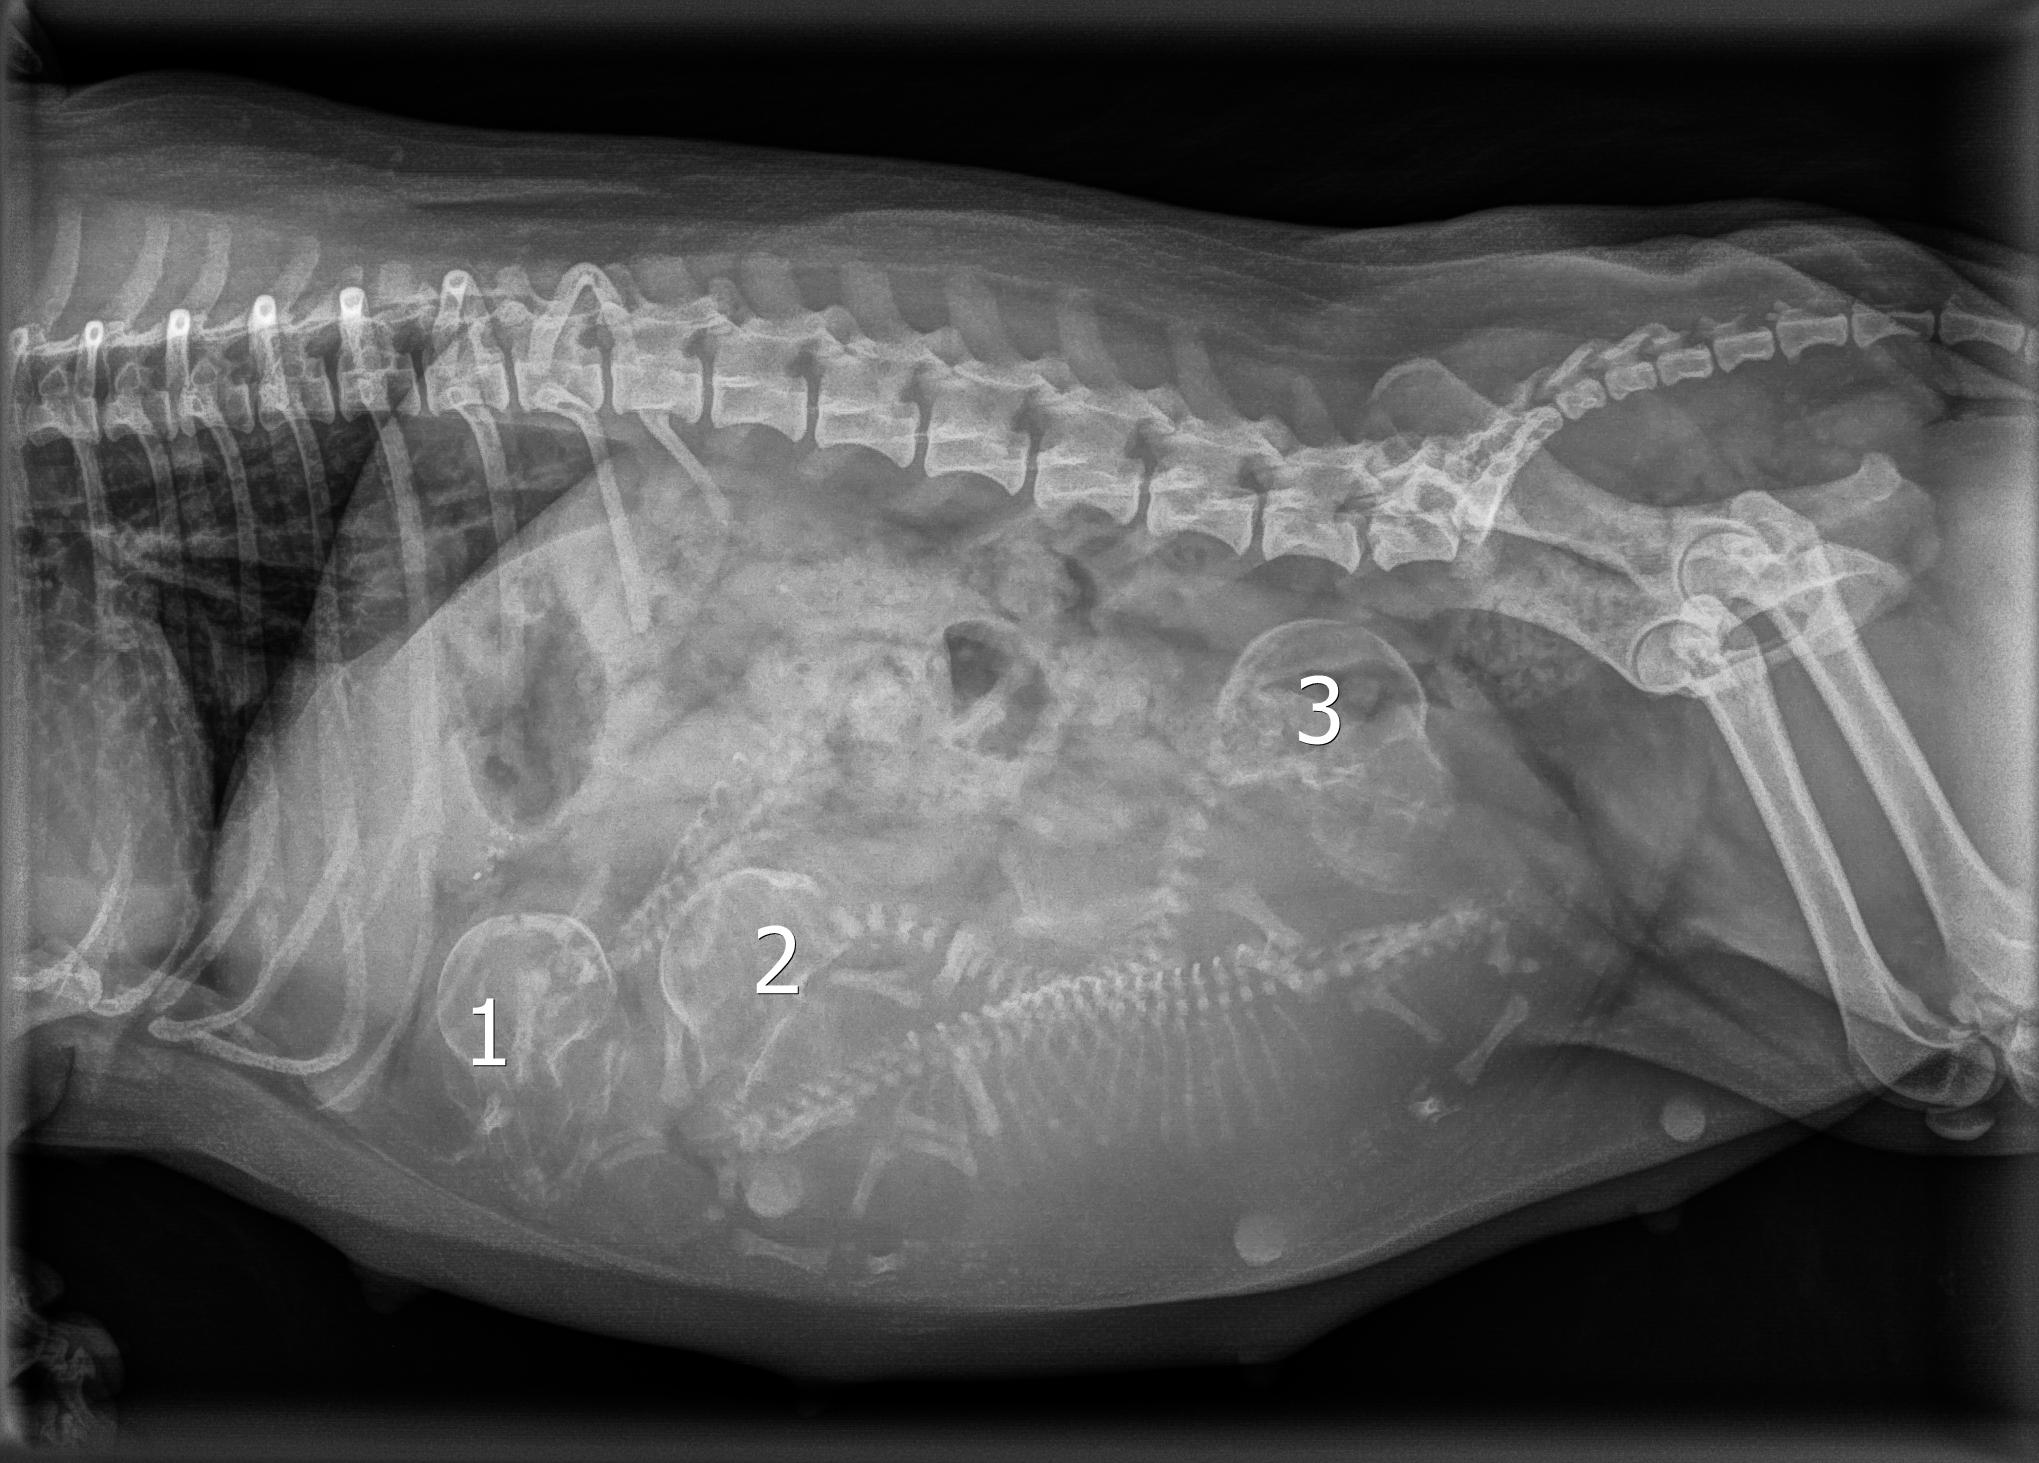

Uit deze combinatie zijn op 12 augustus 2023 3 pups geboren; 2 teefjes en 1 reutje: